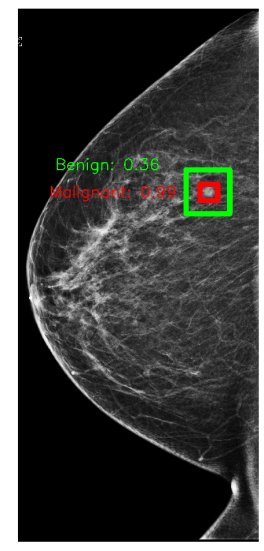

Figure 1: An example of an annotation of a malignant lesion (left) and predictions (right) from a X-101 model on a test set breast.

In Figure 1, we show an annotation and the corresponding prediction using an X-101 model. The model accurately predicts a malignant lesion with high probability (0.99). It also predicts a benign lesion with low probability (0.36) for which there is no ground-truth annotation. These bounding boxes can highlight suspicious regions and help radiologists understand predictions from our models.